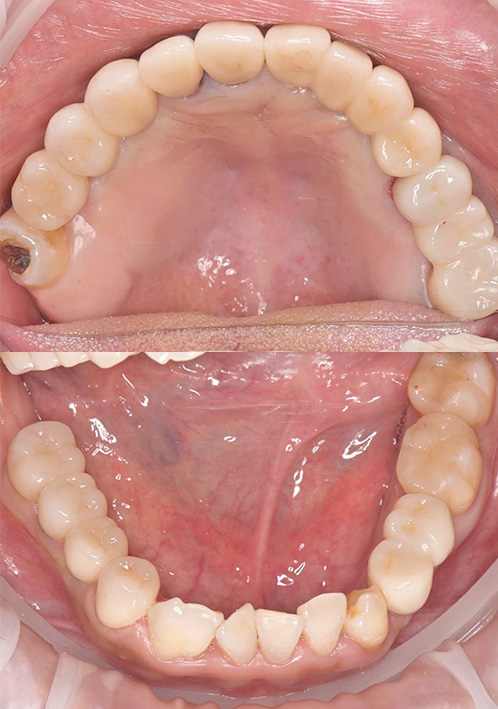

- 短期集中治療による治療例⑥

-

治療本数:20本

治療期間:10ヶ月

歯周病治療・歯周外科治療 インプラント治療併用■治療前 正面

↓ ■治療前 かみ合わせ

↓ ■治療後 正面

■治療後 かみ合わせ